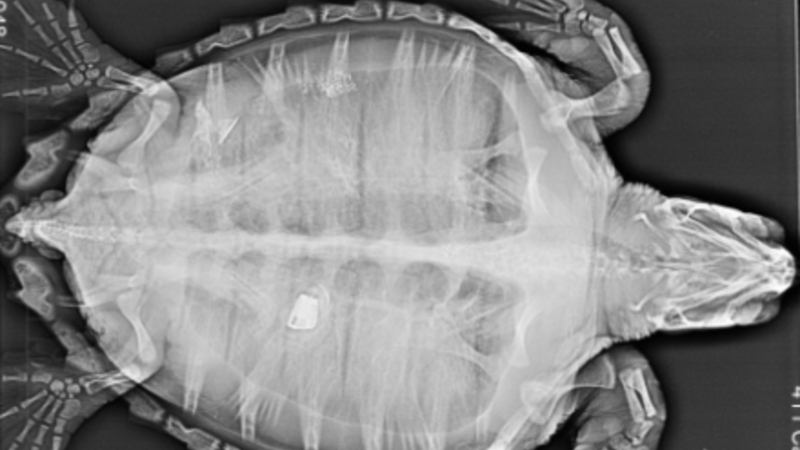

Dyrlægerne hos akvariet gjorde store øjne, da de gav skildpadden en ultralydsscanning og så, hvad der lå og rumsterede i dens tarm.

Det lille dyr havde nemlig gumlet et stykke af en lighter i sig, og det kom der et noget spøjst røntgenfotografi ud af:

Nederst i billedet kan man se det lille stykke lighter, som drillede padden